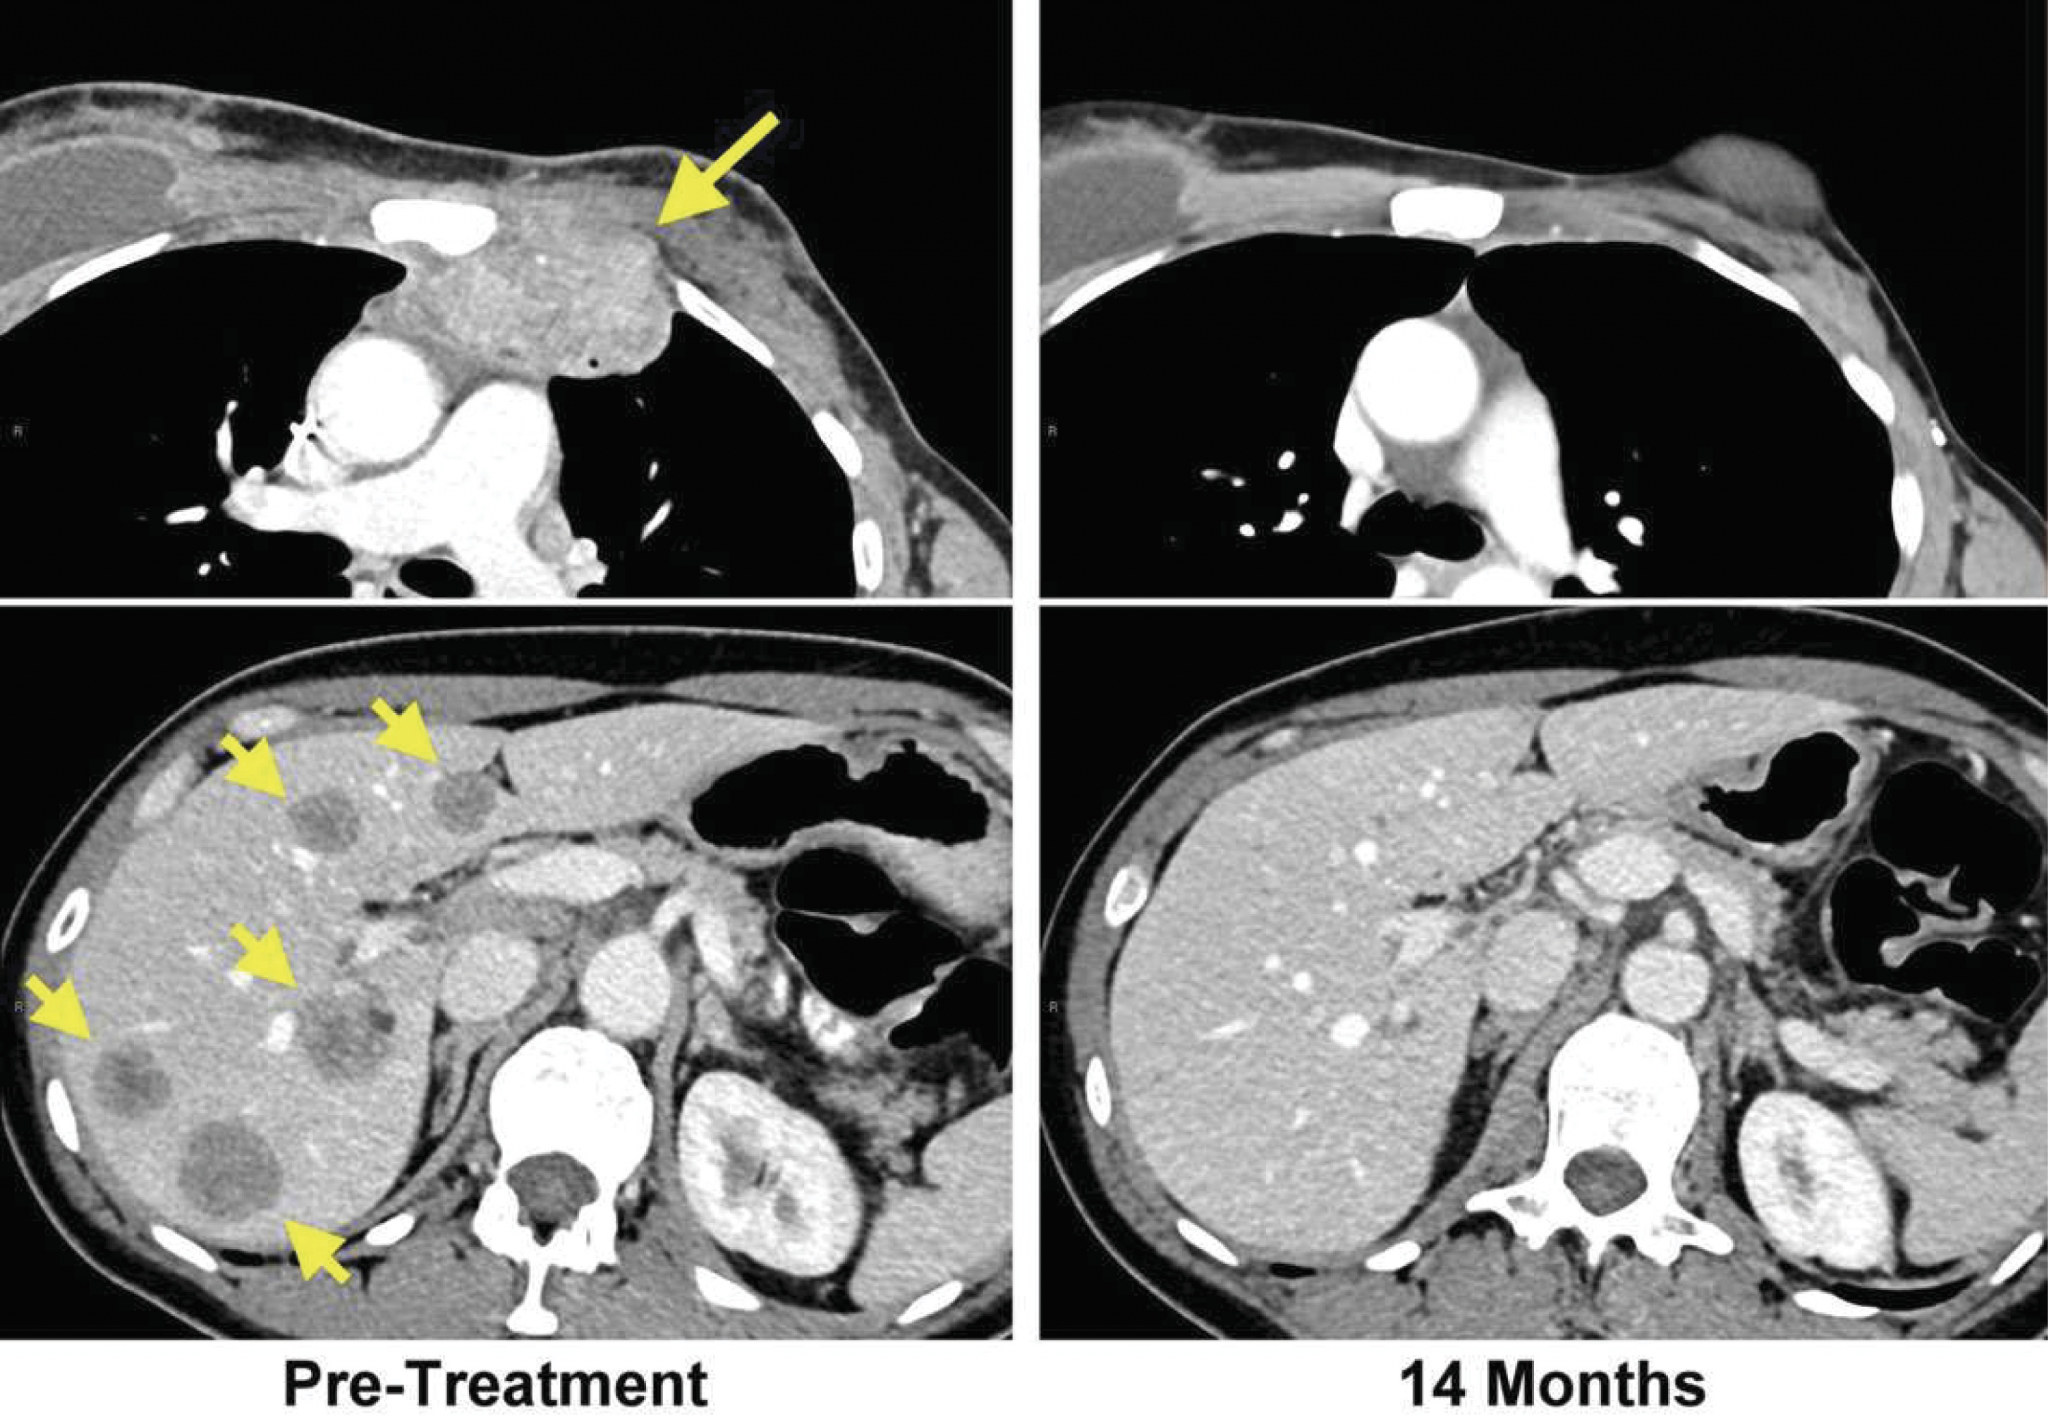

Доброкачественная опухоль. Доброкачественныеопкхоли. Клетки, образующие доброкачественную опухоль:. Строение доброкачественной опухоли. Гиповаскулярные метастазы печени кт. Опухоль желудка метастазирование.

Гиповаскулярные метастазы печени кт. Опухоль желудка метастазирование. План обследования ободочной кишки. Диагноз опухоли ободочной кишки. Диагностические методы исследования ободочной кишки. Алгоритмы диагностики заболеваний толстой кишки.

ПЭТ кт томограмма. Кт, ПЭТ И ПЭТ/кт. ПЭТ кт с контрастом. Скопление контраста ПЭТ кт. Метастатическое поражение печени. Метастатические опухоли печени. Злокачественные образования печени.

Метастатическое поражение печени. Метастатические опухоли печени. Злокачественные образования печени. Молочная железа маммография. Мастопатия на маммографии. Опухоль молочной железы маммограмма. Рик молочной железы маммографич.